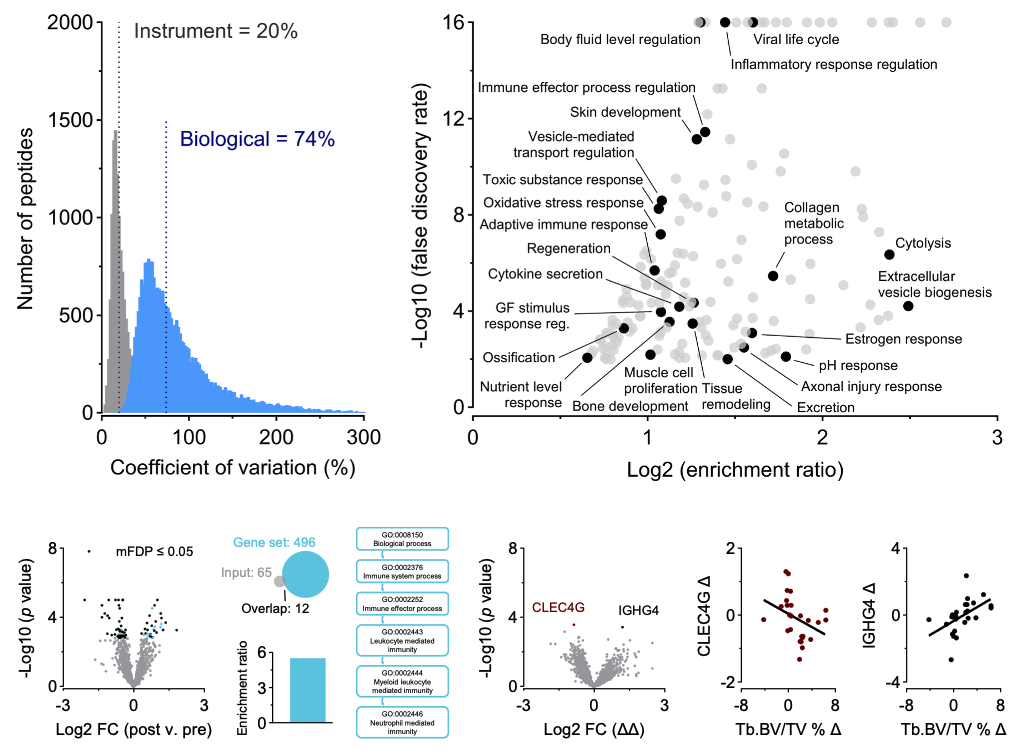

The INBRAIN Laboratory advances human performance through rigorous, innovative, and highly interdisciplinary experimental research. We integrate neuromodulation, multimodal neuroimaging, molecular biology, biomechanics, psychometrics, and wearable sensing to determine how the brain and body adapt to behavior, experience, stress, and injury. Our collaborations across academia, medicine, and the military translate mechanistic insight into actionable approaches that strengthen readiness, enhance recovery, and improve human capability.